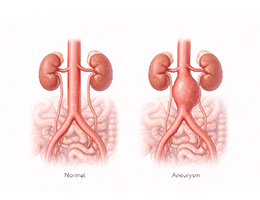

대동맥류(복부) (Abdominal aortic aneurysm)